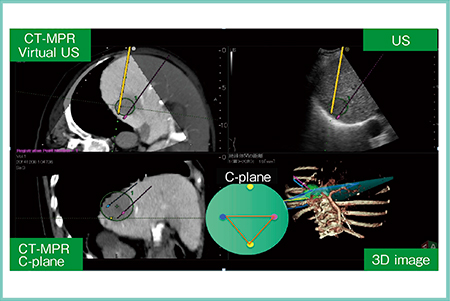

具体的には,超音波画像と同期させたCTやMRIのMPR画像上に複数の電極針穿刺のシミュレーションを可能とし,C-plane画像(穿刺方向と直交する断面)および3D透過画像(3D image)の表示や,各電極針間の距離も表示されるため(図1),電極針相互の位置関係の把握を容易にする。また,同シミュレーション画像と穿刺のシミュレーションラインをナビゲータとして,リアルタイムに電極針の穿刺が可能である。

図1 3D Sim-Navigatorの表示画面